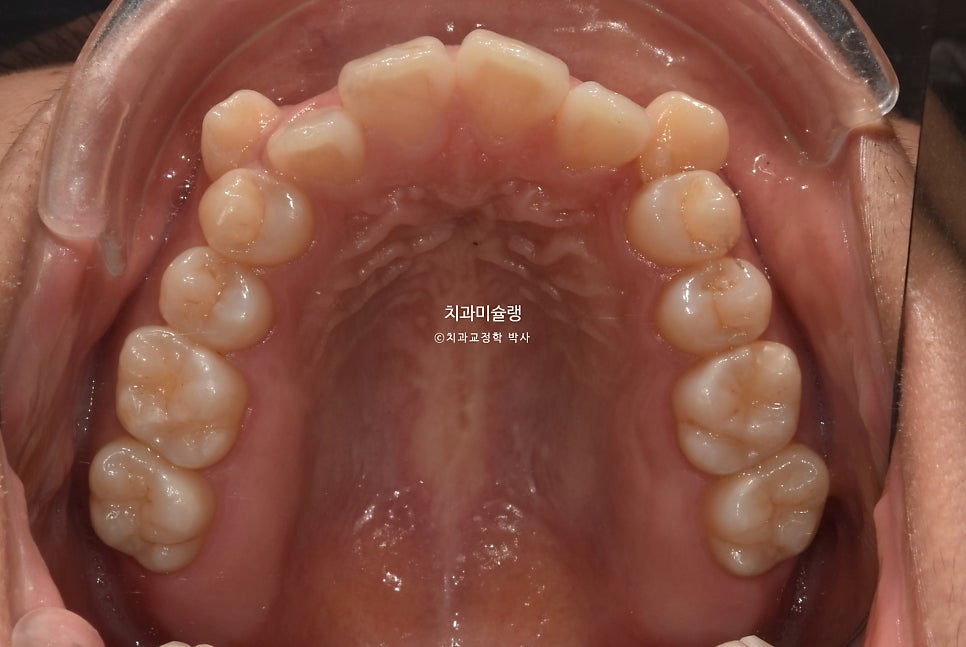

어금니 교합은 좋으며 1급 교합관계를 보입니다.

유지장치까지 잘 들어간 모습입니다.

치료 전반에 걸쳐 치간삭제는 하지 않았습니다.

2년 5개월간 치근흡수는 없었으며

마지막 재제작으로 인해 치근 평행도까지 완벽해졌습니다.